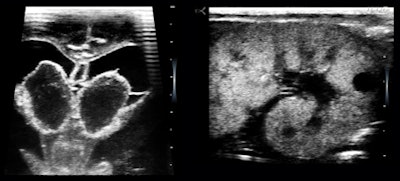

I was into transfontanelle scanning of preemie brains in the later 1970s. Studies done in the NICU have always been my clinical favorites, and their loss was my main regret when I moved to exclusive ambulatory outpatient work at the end of the 1980s. I liked the idea of an instant-starting, battery-operated, small unit for NICU use, and I visited one of the premier units in the Midwest.

I learned from my colleagues that the Children's Hospital of Philadelphia (CHOP) has been offering courses in neurosonography for neonatologists, and there is a groundswell of interest in neonatologists taking over this clinical application themselves. There was no ultrasound equipment available in the nursery I visited, however.

When they needed a study, a request was made to someone in radiology, who would dispatch a technologist, who would in turn lug a wheeled ultrasound unit there. Reports were provided electronically and quickly, but there were frequent disputes about interpretations based on images without direct clinical correlation. In addition, my colleagues expressed a need for identifying pneumothorax and for monitoring intravascular line and endotracheal tube placements, situations that need to be done instantly when the occasion arises.

The NICU is brimming with the most highly educated, proficient, and hardworking talent in the medical world. I have always felt that neonatologists should be scanning their own patients and that they should be able to look whenever they thought it might alter their management plans. When I used the U-Lite, I was interacting directly with neonatologists who intimately knew the babies I scanned, so we could go directly to the issues of immediate medical concern.

The lesson here is that just leaving an ultrasound unit in the NICU to be used by a technologist and interpreted elsewhere is not good enough. In this "conventional" mode, ultrasound tends to be used to confirm a clinical suspicion, not for identifying early signs or treatment surveillance.

Inasmuch as newborns can be anything from a 350-g preemie to a 5,500-g macrosomic infant, I thought their needs would best be served with a laptop unit on a small mobile cart, permanently and always stationed in the NICU, with a full complement of high-frequency transducers with different configurations.